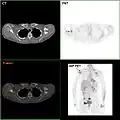

As seen on the image above the breast is already affected with cancer